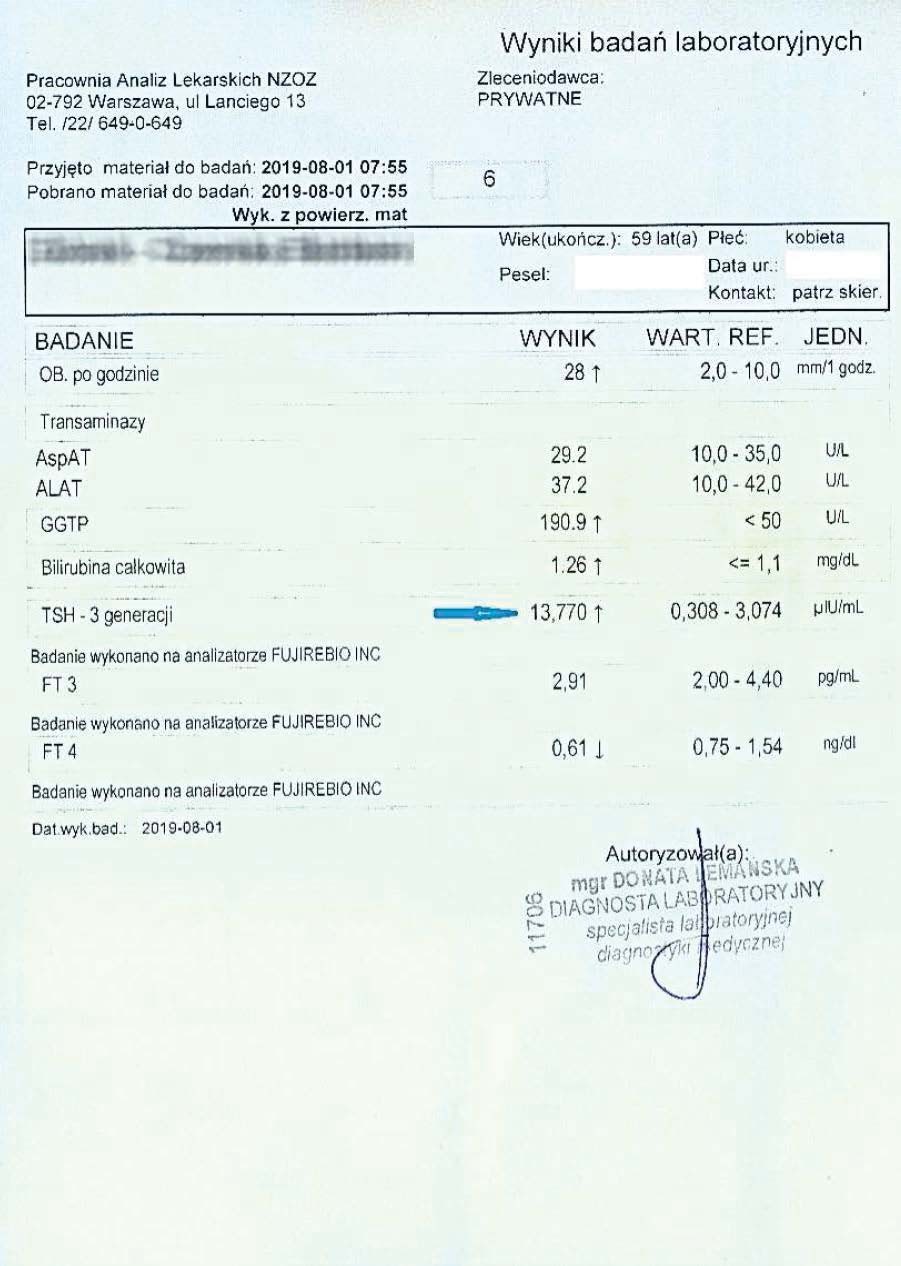

PRZYKŁAD EFEKTU PREPARATU NA NIEDOCZYNNOŚĆ TARCZYCY

Kobieta lat 59 z niedoczynnoscią tarczycy, bez przyjmowania lewotyroksyny. Kobieta przyjmowała preparat przez okres ponad 3 miesięcy. Przy zachowaniu naturalnego cyklu komórkowego i stałemu stymulowaniu mitochondriów osiągneła następujące wyniki kuracji:

Po zaobserwowaniu znacznej poprawy w ogólnym samopoczuciu, kobieta postanowiła wykonywać badania ze zwiększoną częstotliwością oraz kontrolę prób wątrobowych.

Po kolejnych dwóch miesiącach kobieta ponownie wykonała badania. Widoczne są: spadek TSH, obniżenie stanu zapalnego jak i spadek markeru wątrobowego GGTP.

Sukcesywnie co 2 miesiące można zaobserwować stały spadek parametrów zarówno wątroby jak i tarczycy. Kolejne badania potwierdzały dalszy spadek parametrów.

Po ponad roku kuracji badania wykazały dalszy postęp wycofania autoimmunologi tarczycy, potwierdzone również badaniem USG narządu.

Preparat wpływając na odbudowę mitochondriów zapewnił podłoże energetyczne do produkcji hormonów i odbudowy narządu. Brak ingerencji farmakologicznej wykazuje skuteczność nawet w podeszłym wieku, gdzie regeneracja jest wolniejsza a reakcje anaboliczne w znacznym stopniu spowolnione. Można zaobserwować także działanie ogólnoustrojowe obserwując spadek markeru wątroby, co jasno wykazuje poprawę funkcjonowania całego organizmu.